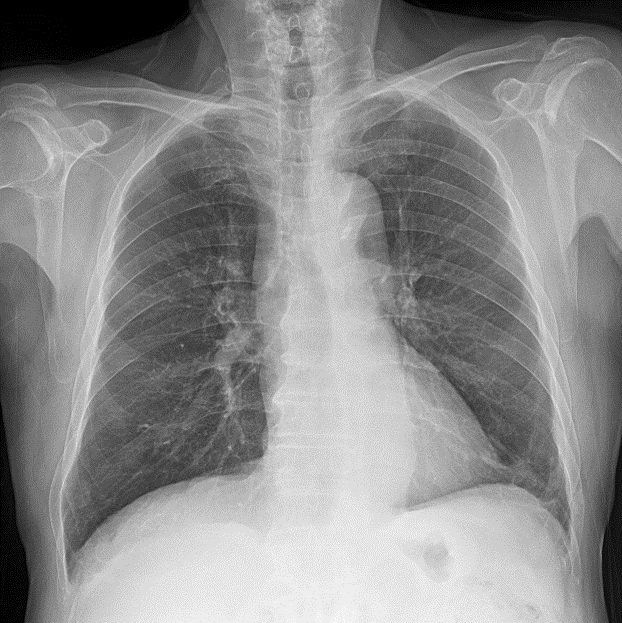

심장질환 분야에서 가장 보편적으로 활용되고 있는 심초음파 검사와 관련하여 다양한 AI 연구개발에 활용될 수 있는 관련 임상의료데이터 및 경흉부 X-ray 데이터

정확하고 효율적인 의료서비스를 지원하는 AI기술 개발이 가능하도록 심장질환 분야에서 일차적으로 활용되는 심전도 및 심초음파 데이터와 그 활용성을 극대화 할 수 있는 유관 데이터를 포함하는 ‘학습용 표준 빅데이터’를 구축

| 원천데이터(DICOM) |

![]() |

| id | "0118610_cxr" |

| file format | ".dcm" |

| width | 2017 |

| height | 2017 |

| study date | “2018.03.26” |

| patient_id | “0118610” |